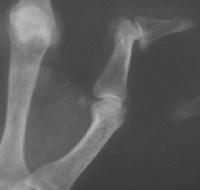

Clinical Example: Rheumatoid arthritis

rheumatoid hand